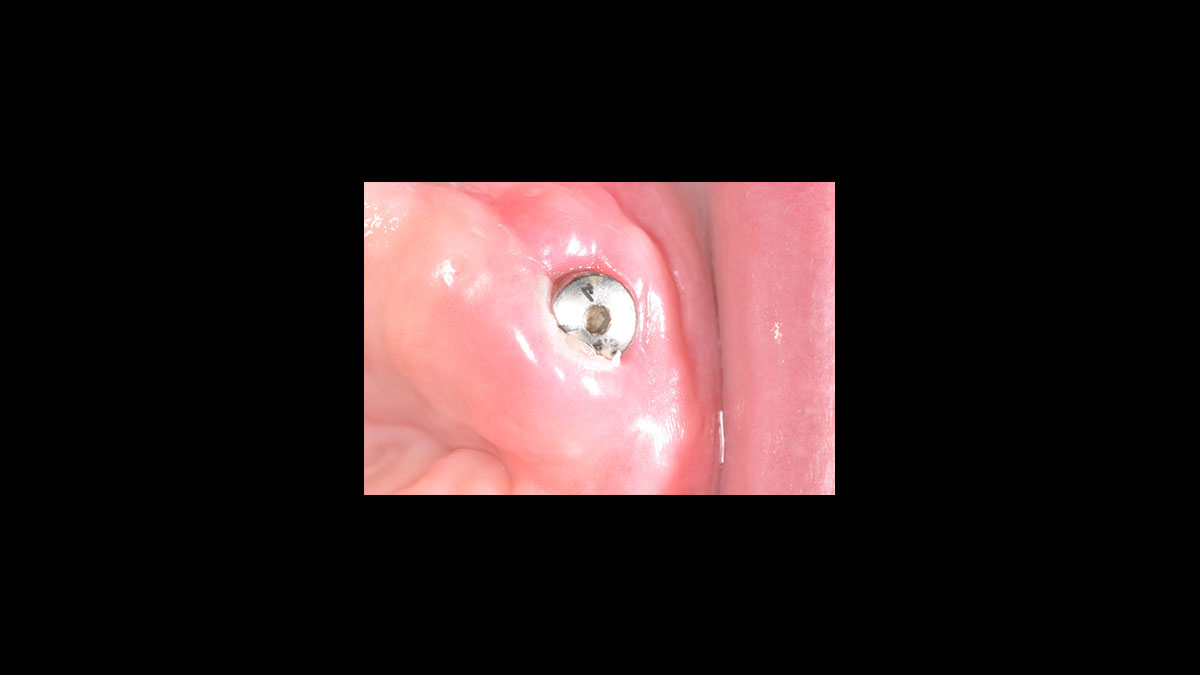

Implant uncovery